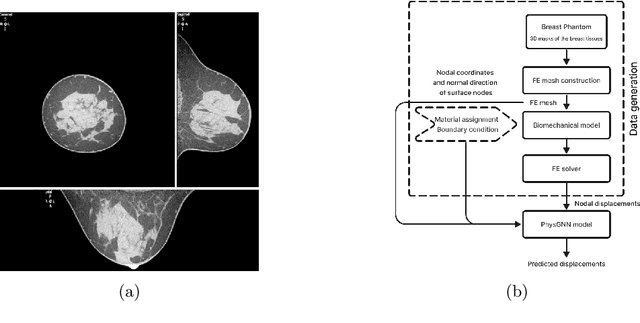

Abstract:Breast compression simulation is essential for accurate image registration from 3D modalities to X-ray procedures like mammography. It accounts for tissue shape and position changes due to compression, ensuring precise alignment and improved analysis. Although Finite Element Analysis (FEA) is reliable for approximating soft tissue deformation, it struggles with balancing accuracy and computational efficiency. Recent studies have used data-driven models trained on FEA results to speed up tissue deformation predictions. We propose to explore Physics-based Graph Neural Networks (PhysGNN) for breast compression simulation. PhysGNN has been used for data-driven modelling in other domains, and this work presents the first investigation of their potential in predicting breast deformation during mammographic compression. Unlike conventional data-driven models, PhysGNN, which incorporates mesh structural information and enables inductive learning on unstructured grids, is well-suited for capturing complex breast tissue geometries. Trained on deformations from incremental FEA simulations, PhysGNN's performance is evaluated by comparing predicted nodal displacements with those from finite element (FE) simulations. This deep learning (DL) framework shows promise for accurate, rapid breast deformation approximations, offering enhanced computational efficiency for real-world scenarios.